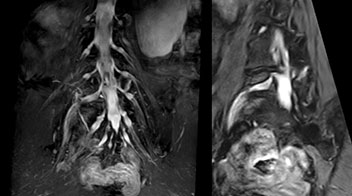

At Northern Fukushima Medical Center in Japan, excellent MRI visualization of nerves helps support confident diagnoses and informs surgical treatment decisions for patients with lower limb symptoms. MRI technologist Tanji and orthopedic surgeon Dr. Yabuki share how direct nerve visualization with the 3D NerveVIEW method adds information when diagnosing atypical herniations. The additional insights changed their way of working and benefit their patient care, as illustrated by some clinical examples.

“In patients with lower extremity neurological symptoms, NerveVIEW helps us to determine the disease matching the patient’s symptoms by directly visualizing the nerves. We use the sequence mainly, when there is suspicion of intraforaminal stenosis, extraforaminal stenosis or lateral disc herniation, which is often based on routine T2- and T1-weighted images. Additionally, the excellent depiction of the course of nerves makes NerveVIEW a good navigator when applying treatment such as block therapy or surgery.”

Northern Fukushima Medical Center (NFMC) Imaging Center uses the 3D NerveVIEW sequence for performing MR neurography, particularly in patients with pain and weakness in the lower limb. “It is included in about 20% of the approximately 150 lumbar spine MRI exams each month at NFMC, and can help us to determine if structures are impinging on the nerves,” says Hajime Tanji, RT, MRI technologist at NFMC.

The addition of the nerve-selective NerveVIEW sequence to its spine MRI protocol has given NFMC competitive advantages, according to Tanji. “Since we started including NerveVIEW routinely, the demand for lumbar spine MRI examinations has increased, especially for pre-surgical planning purposes and for patients with chronic lower extremity symptoms,” he says. “Moreover, because no other hospitals in our region are doing nerve plexus imaging yet, we often receive referrals for MR neurography studies from other hospitals even if they have an MRI scanner. Some requests come from as far as 100 km away. NerveVIEW definitely provides us a competitive advantage.” “Based on our experience, we can certainly recommend NerveVIEW to other centers,” Dr. Yabuki adds. “The sequence opens up many possibilities to facilitate the diagnosis of lower extremity pain and to inform our decision-making regarding therapy and surgery.”